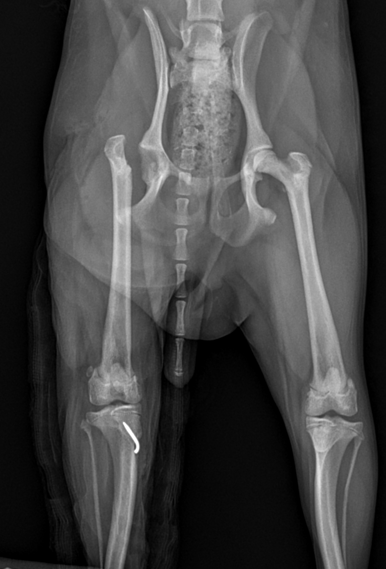

• 슬개골 탈구 3기 이미지

양측 수술 슬개골 탈구 3기

양츨 슬개골 탈구 3기, 십자인대 손상 전

빠른 수술 후 회복까지!